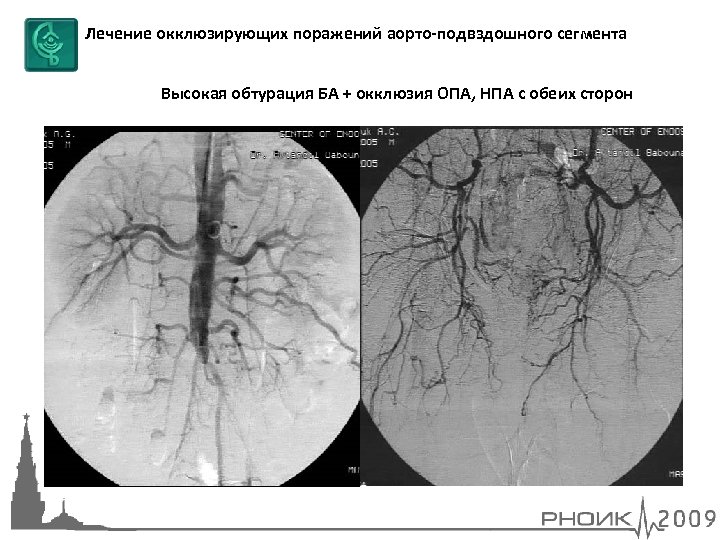

Лечение окклюзирующих поражений аорто-подвздошного сегмента Высокая обтурация БА + окклюзия ОПА, НПА с обеих сторон

Лечение окклюзирующих поражений аорто-подвздошного сегмента Высокая обтурация БА + окклюзия ОПА, НПА с обеих сторон ЧТА БА, ОПА и НПА с двух сторон